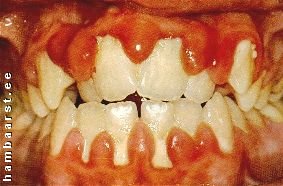

Kui igemepõletikku ei ravita (hambakattu ja kivi ei eemaldata), hakkab hammaste kinnituskude hävima. Ige irdub hamba küljest, tekivad sügavad igemetaskud, kuhu asuvad elama lõaluud hävitavad pisikud.Hambajuureümbrise põletiku ehk parodontiidi puhul lisandub lisaks igemeverejooksule ja ebameeldivale hingeõhule ka igemeturse, mädakolded igemetaskus ning hammaste liikuma hakkamine. |

Hambakivi moodustub enamasti hammaste vahele, kust hambaharjaga pole kattu võimalik eemaldada. Hammastele ohtlikum on igemetaskuvedeliku kaasabil tekkiv igemealuse katu kivistumine. Tekkiv igemealune kivi kasvab järjest sügavamale hambajuure tipu suunas, kuni hambad hakkavad liikuma ja irduvad lõualuust.